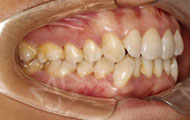

2017-9-23 矫正过程中

平时我有大量的出差和节目录制,但牙套一点都没有影响到我的工作,甚至戴着牙套说绕口令都没有问题。而且接近一年的矫正能看出来牙齿有改变,我吃饭的时候能感觉到对牙齿的卡塞程度、包括次数、频率这些都是在缓慢的减少和降低。